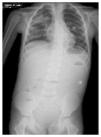

In the ultrasound of the cervical region carried out on February 23, 2012, there were multiple adenopathies identified on the right side of the lymph node chain. The Doppler effect showed a higher vascular flow and displacement of the adjacent vascular paths. On the left side there were lymph nodes >1 cm in size and similar to the right side showing a greater vascular flow in its center (Fig. 1). Simple chest x-ray of November 19 showed normal characteristics. Only a volume increase in both cervical regions in relation to lymph node growth was identified (figure not shown).

Figure 1 Ultrasound image in the cervical region bilaterally. Multiple adenopathies are observed at this level which, according to the Doppler effect, showed an increase of the flow within. (A) Left side. (B) Right side.